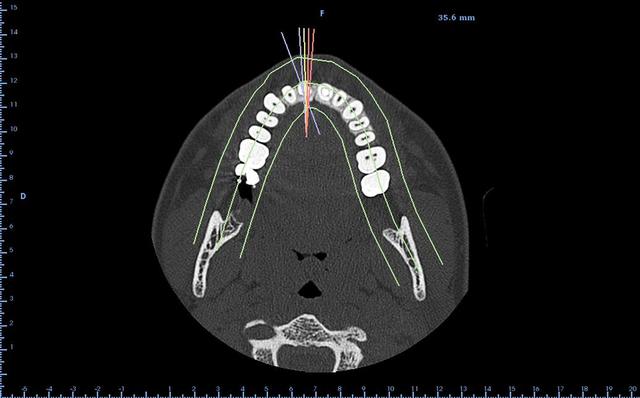

encore un ptit cas...sympa si on veut...car là j'ai besoin de l'expérience de ceux qui font çà souvent...

patient 17 ans...bientôt 18...

trauma dans l'enfance sur 11 et 21

pour la 21, çà va...mais la 11 est à bout de souffle...avec l'apex qui traverse la gencive vestibulaire...

veut un implant...forcément...mais là, faut une greffe...plutôt importante...

Tu n’a pas un couloir suffisent entre les corticales pour placer un implant avec des vis à compression ?

Sinon concernant ton cas j'ai l'impression qu'il y a de l'os en mesial et distal de ta dent du coup si c'est bien le cas je ferais de la rog avec une membrane pinsee